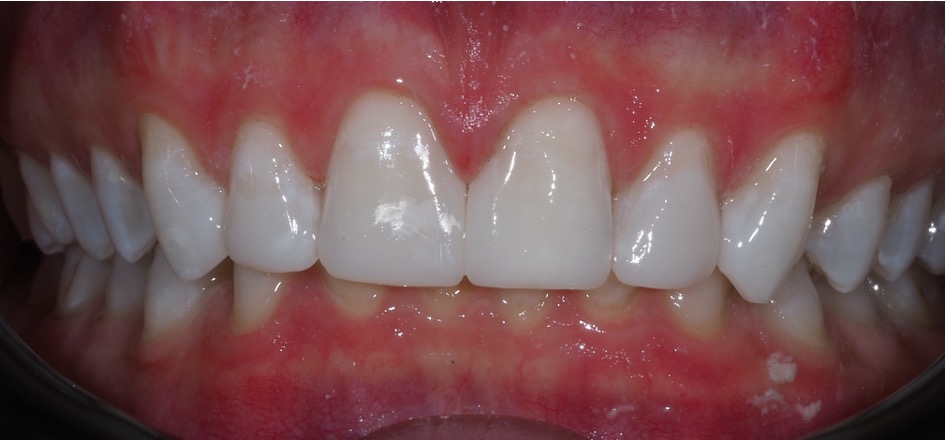

Composite bonding can also be carried out to close spacing and change the colour of teeth particularly when orthodontic treatment is not desired and tooth whitening has been attempted.